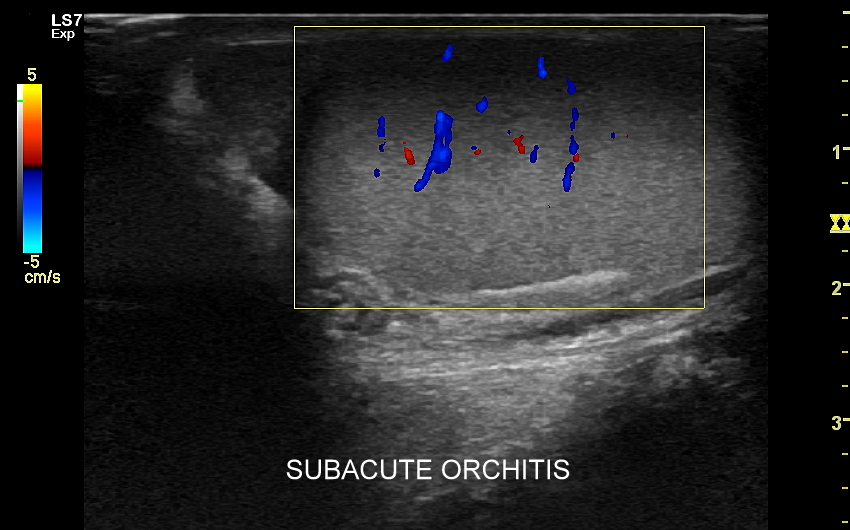

Najczęstsze choroby w obrębie moszny obejmują żylaki powrózka nasiennego, zapalenia jąder i najądrzy, wodniaki jądra, skręty szypuły jądra bądź przydatków jądra, torbiele najądrzy, nowotwory i raki jąder. Niezależnie od powyższego u chłopców spotyka się wnętrostwo, czyli niepełne zstąpienie jądra do moszny, które to może pozostać w jamie brzusznej lub pachwinie, a także ektopię jąder, czyli ich zabłąkane położenie (np. w okolicy krocza).

USG moszny i kanału pachwinowego jest podstawową metodą obrazowania jąder, najądrzy, powrózka nasiennego, w tym nasieniowodu oraz towarzyszących im naczyń żylnych i tętniczych. Badanie USG przeprowadzić należy w przypadku wystąpienia bólu i obrzęku jąder, pojawienia się macalnego guzka w obrębie moszny, podejrzenia skrętu lub zapalenia jądra, żylaków powrózka nasiennego, w ramach oceny dojrzewania płciowego chłopców. Kanał pachwinowy bada się także w sytuacji podejrzenia wnętrostwa, przepukliny pachwinowej, w celu oceny węzłów chłonnych, a także nasieniowodu w diagnostyce niepłodności męskiej.

Mosznę bada się aparatem USG wyposażonym w dedykowaną sondę o wysokiej rozdzielczości przeznaczoną do oceny jąder i drobnych struktur moszny, koniecznie z zastosowaniem trybów dopplerowskich, takich jak Doppler kodowany kolorem, Doppler spektralny i obrazowanie mikrounaczynienia. Dopełnieniem badania USG jąder jest użycie w stosownych przypadkach trybu elastografii oraz trybu USG z kontrastem (CEUS). Lekarzem, który pierwszy we Wrocławiu i na Dolnym Śląsku przeprowadził badanie CEUS jąder jest dr Tomasz Szczepański.